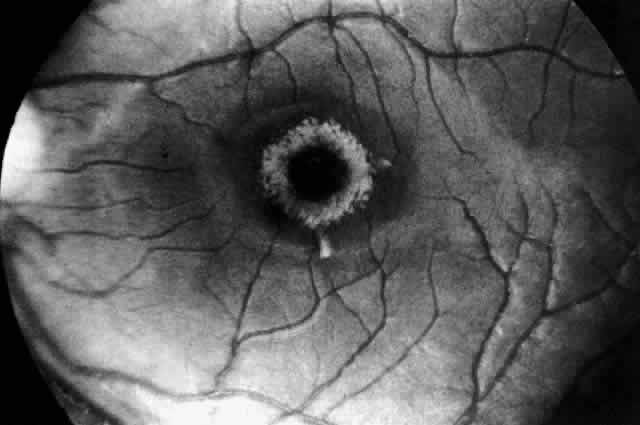

In three patients with type III subacute juvenile neuronopathic Gaucher's disease however, the retina showed a unique retinopathy. The findings in Cogan's case 1 are described: “Both fundi showed discrete white spots randomly distributed in the posterior fundus, especially along the inferior vascular arcades (Fig. 8). The spots varied in diameter from just visible to approximately 0.1 mm and were situated in the superficial retina or on the surface of the retina. Several covered the retinal vessels. The disc and retinal vessels were normal.” The child, an 11-year-old boy, had normal acuity and a full field of vision by confrontation. He had presented at age 3 years with splenomegaly.

Fig. 8. Fundus of a patient with type III subacute juvenile neuronopathic Gaucher"s disease showing discrete white spots in or on the retina along the inferior vascular arcades. At least one spot overlies a vein. The optic disc and retinal vessels were normal. (Cogan DG, Chu FC, Gittinger J, Tyshsen L: Fundal abnormalities of Gaucher"s disease. Arch Ophthalmol 98:2202, 1980. Copyright © 1980, American Medical Association)

Normal vision and similar retinal abnormalities were observed in a mildly mentally retarded 18-year-old woman (case 2) presenting with splenomegaly at age 1 year and in a 6½-year-old boy (case 3) noted to have hepatosplenomegaly in the first year of life. The patients in cases 1 and 3 had conspicuous supranuclear defects of eye movement.